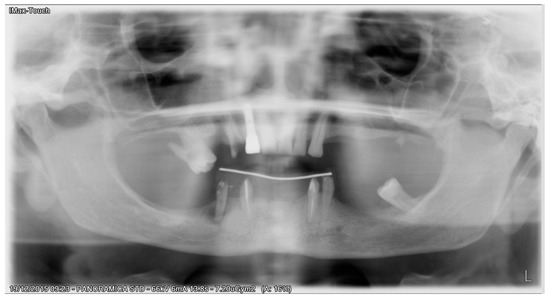

Figure 7. 2 years postoperative panoramic X-ray.